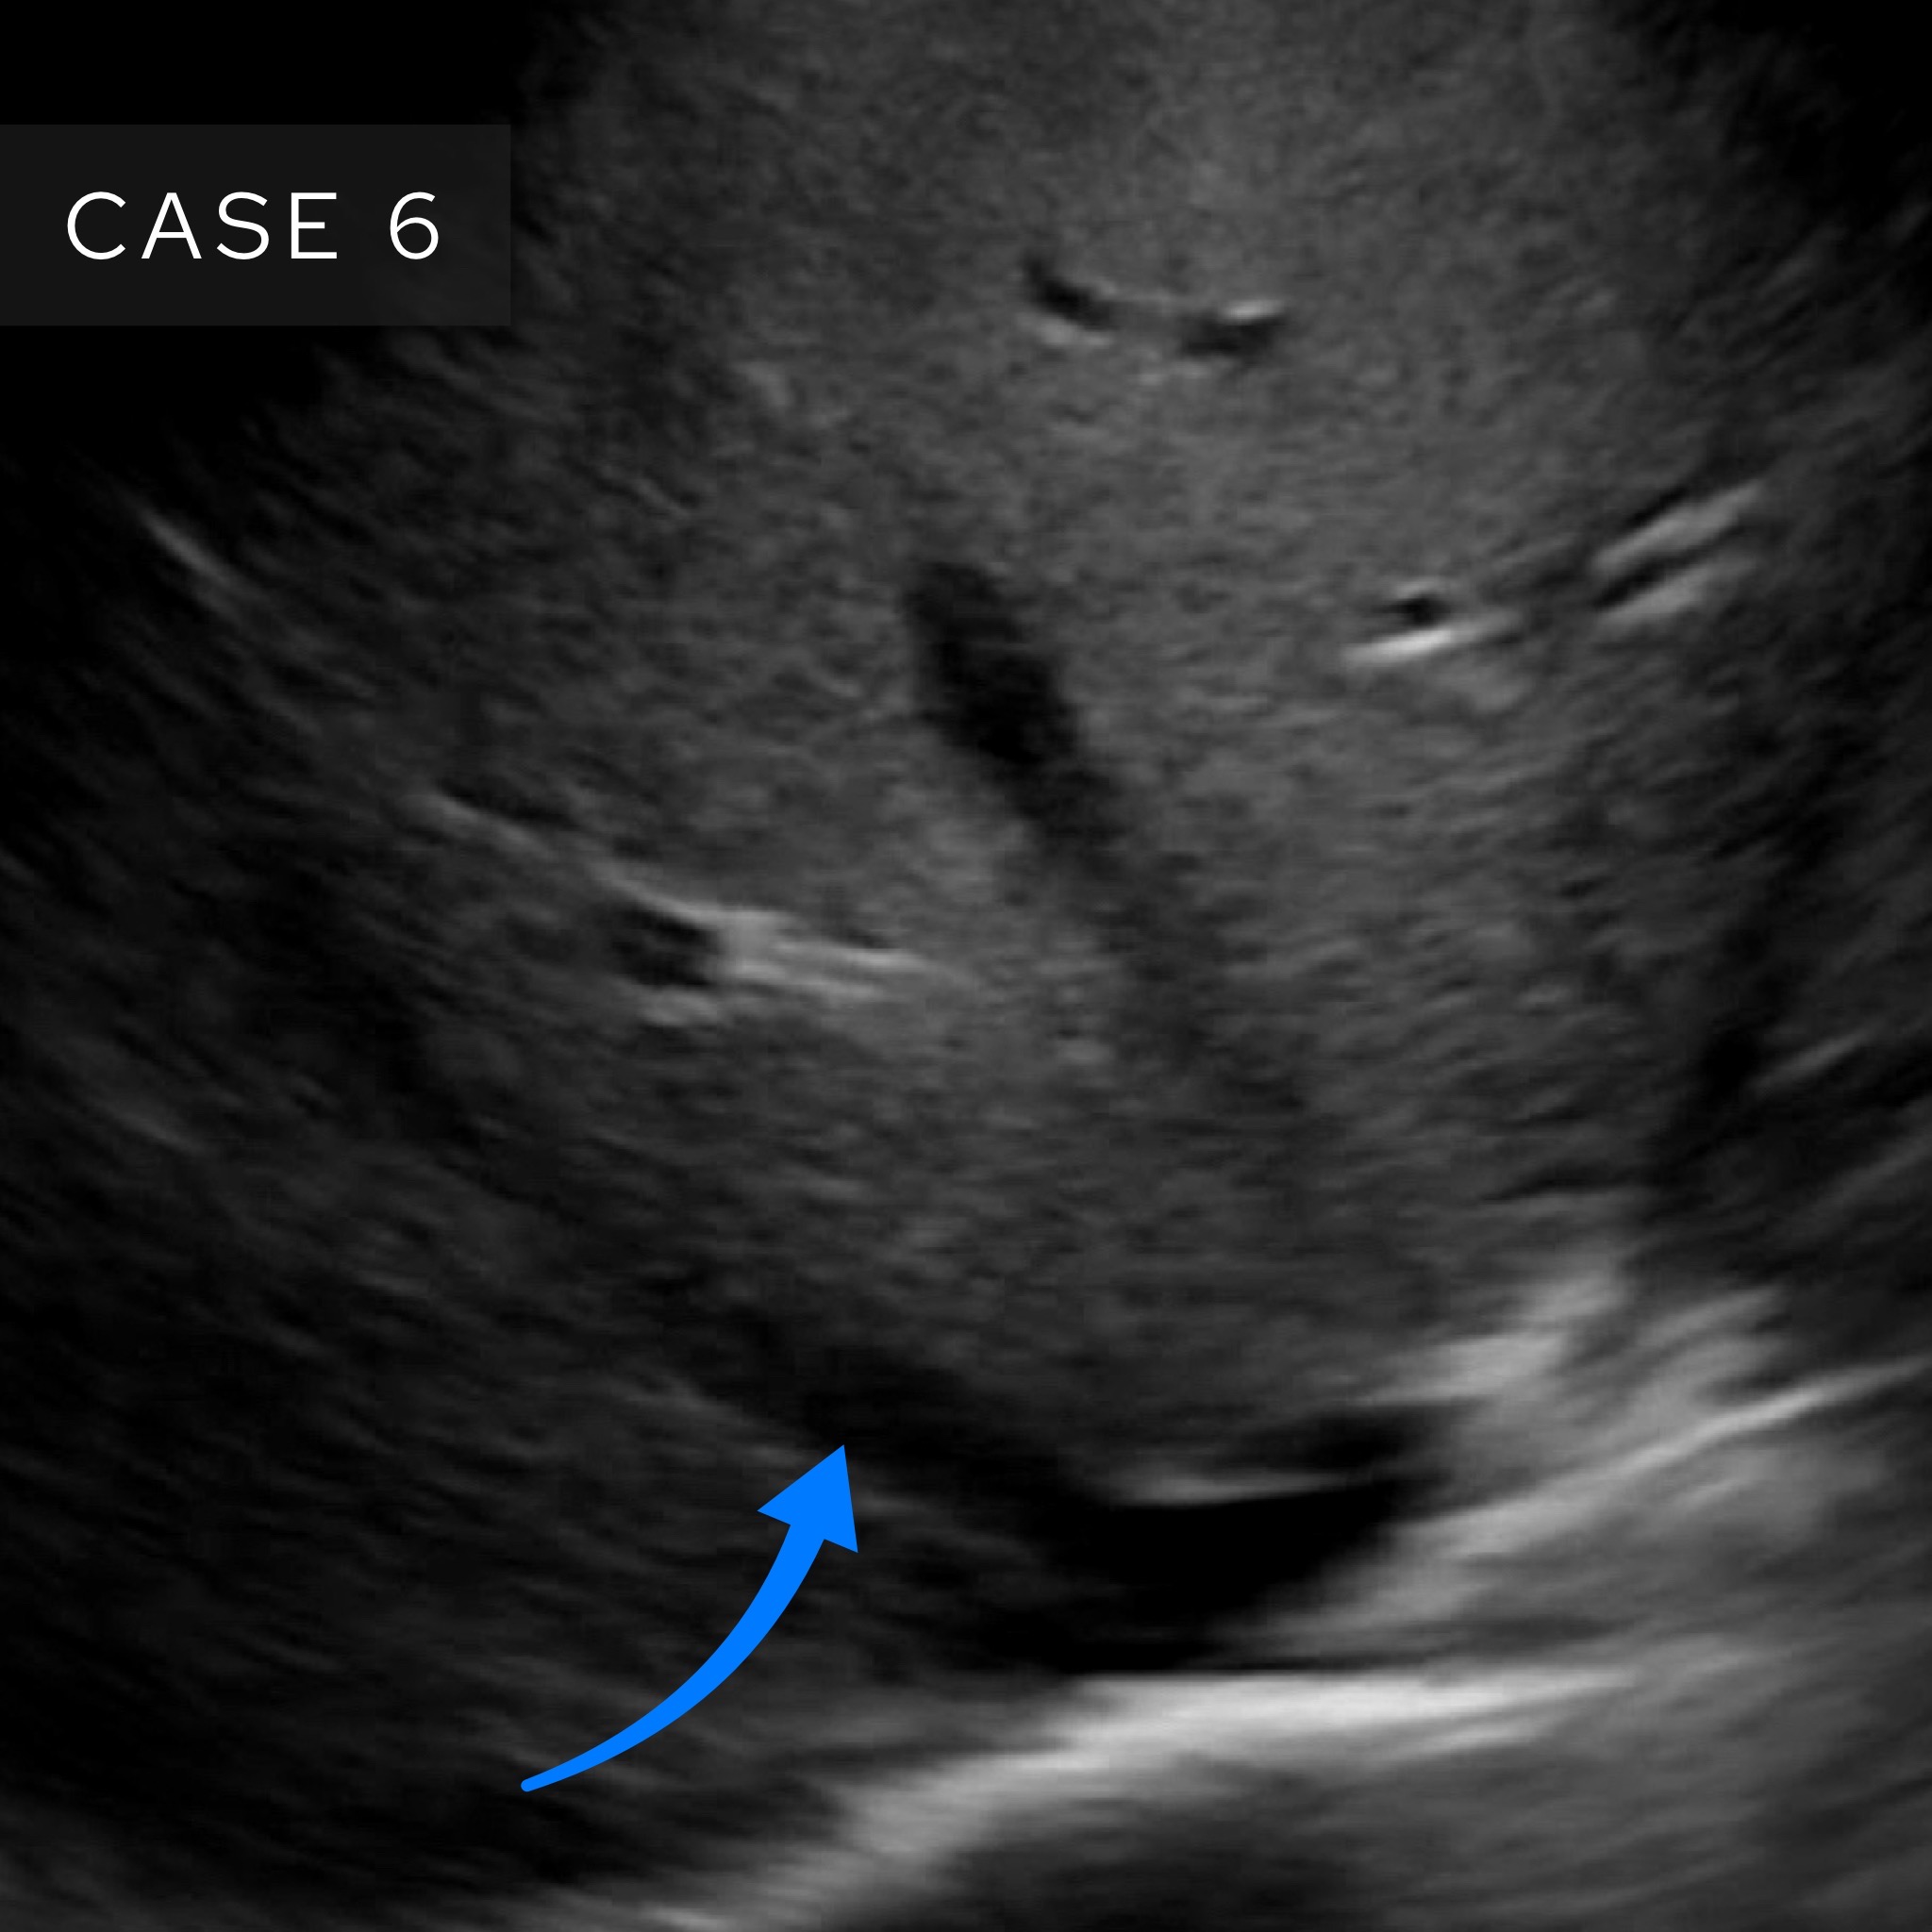

Case 6

This time we’re going to look at an ultrasound. What is the arrow pointing at here?

Answer: Right hepatic vein

This is an image of an ultrasound of the liver. We are near the top end (superior) of the liver. How do we know this? We can see the hepatic veins – these drain into the inferior vena cava at the superior end of the liver.

The hepatic veins drain into the inferior vena cava at the superior end of the liver

This image is a nice depiction of the hepatic veins and an image I try and see every time I do a liver ultrasound. I get the picture by placing the probe under the right costal margin (below the ribs anteriorly) and asking the patient to take a gentle but deep breath in before holding. I then fan through looking to find this picture. Don’t forget to let your patient breathe again or you’ll need to set off the crash alarm.

The three hepatic veins look a bit like ‘crow’s feet’ and can be easily distinguished as right, middle and left.

The three hepatic veins look like ‘crow’s feet’ heading towards the inferior vena cava